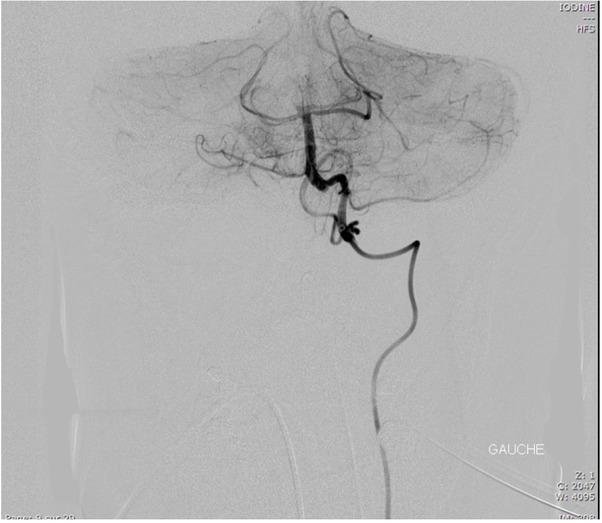

Fig. 3